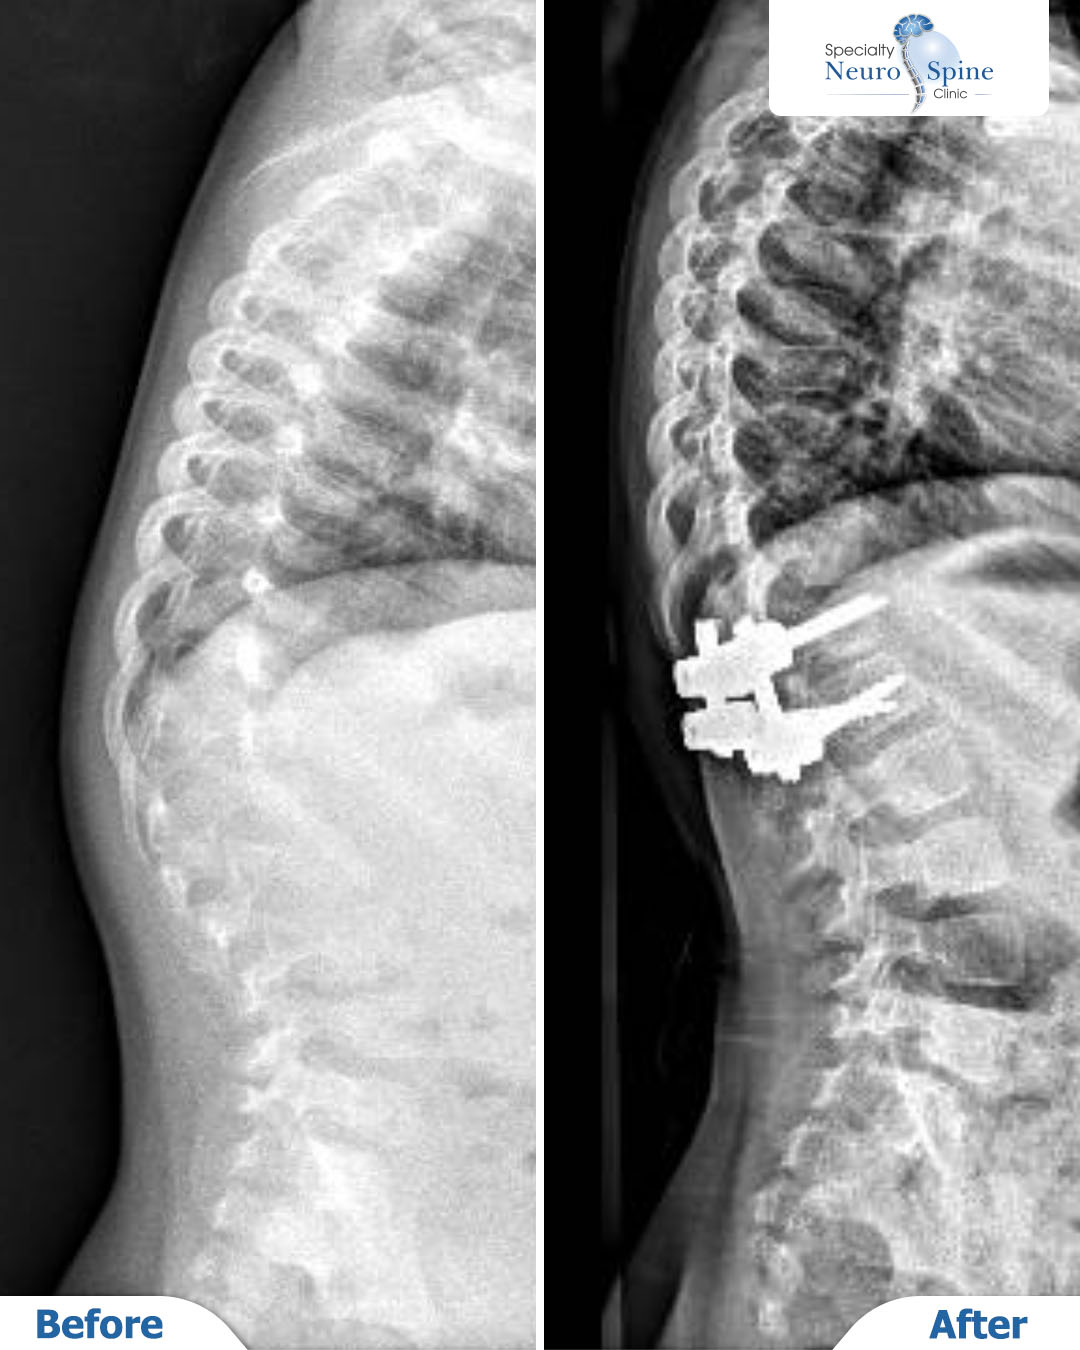

X-ray images showing the condition of our brave patient Sally before and after her spinal deformity correction surgery, which was performed when she was just 3 years old.

The procedure involved correcting the curvature from the twelfth thoracic vertebra (T12) to the first lumbar vertebra (L1). Two years later, the results confirm the success of the surgery, with excellent vertebral alignment and stability.